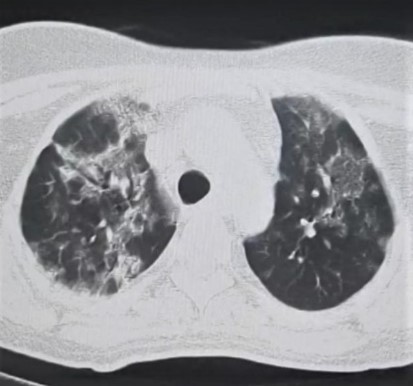

On discharge HRCT